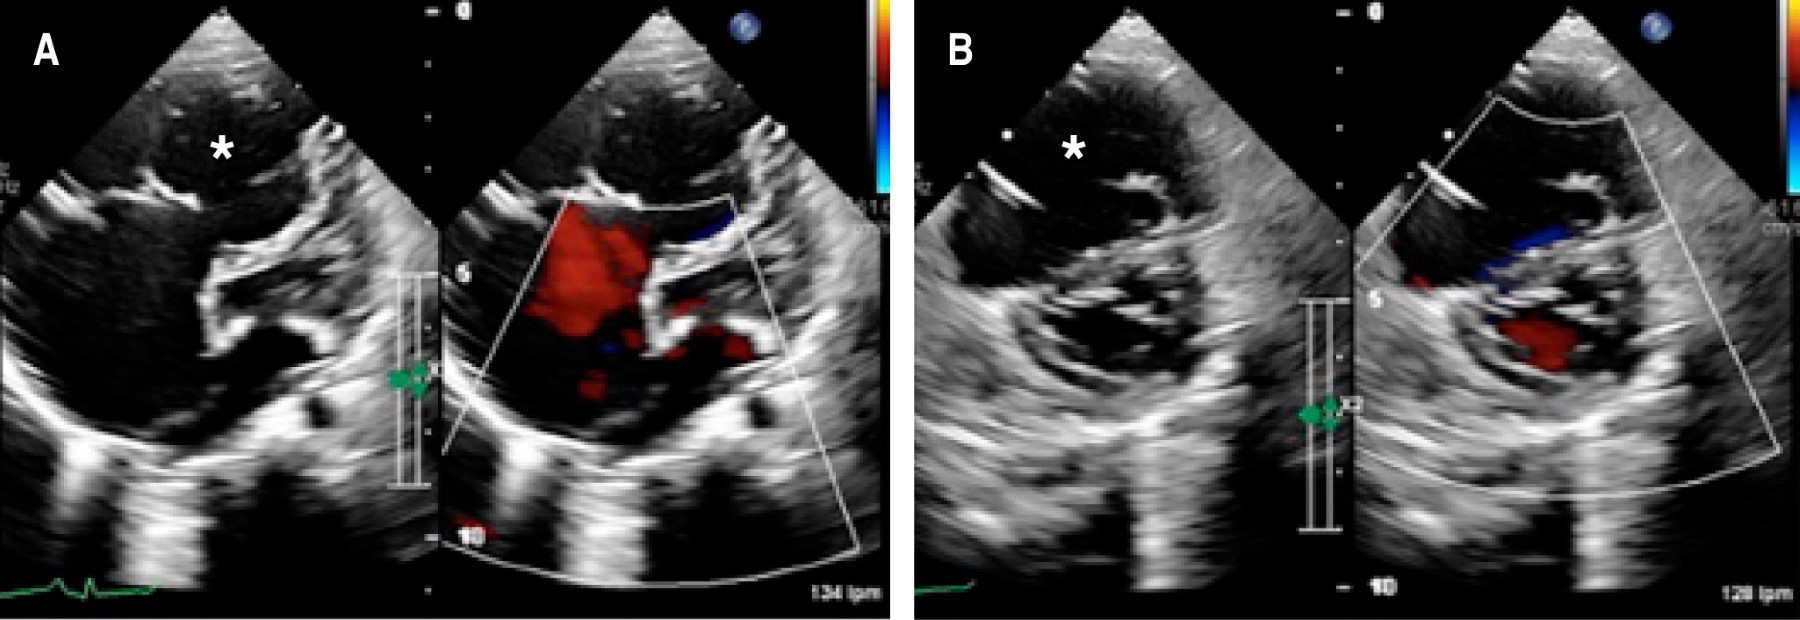

El ecocardiograma mostró una aurícula derecha dilatada de 58 mL/m2 (z-Score: + 2.17) con insuficiencia tricúspide severa, comunicación interauricular de 3.5 mm, con dilatación ventricular derecha 35 mL (z-Score: + 4.16) y disfunción diastólica con TAPSE de 10 mm y fracción de acortamiento del ventrículo derecho de 26% con movimiento septal paradójico (Figura 2).

Durante el abordaje de estos pacientes, la ecocardiografía tiene un rol fundamental para el diagnóstico,2,5,6 al identificar la característica cavidad ventricular derecha grande y dilatada, con una pared ventricular adelgazada sin trabeculaciones apicales e hipocinética. El anillo tricuspídeo suele estar marcadamente dilatado, pero con una anatomía conservada y de implantación normal.2,5,6

Figura 2